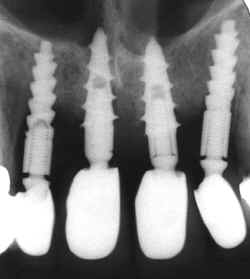

Radiografia sem edição alguma da imagem

evidenciando a trepanação das fossas nasais e conseqüentes reabsorções ósseas.

As

reabsorções ósseas circunjacentes aos implantes também são notáveis.

Observe

a falta de adaptação dos intermediários pelas diferenças de adaptação dos mesmos

entre os quatro implantes.

Nesta

radiografia as aletas dos elemento dentário 22 ainda

não foram colocadas. |